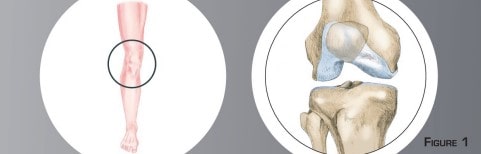

L’arthrose débutante interne est l’usure du cartilage présente entre la partie interne du fémur et du tibia (figure n°2 et photo n°1). La morphologie du membre inférieur en est souvent la cause principale. Sur une forme incurvée, tout le poids du corps passe plutôt par la partie interne du genou (figure n°3). Cette surcharge aboutit à l’usure prématurée du cartilage et du ménisque.

L’axe du membre inférieur ne se corrige pas spontanément et l’usure interne aggrave la déformation du membre, ce qui aggrave davantage l’usure. L’évolution naturelle se fait vers l’usure complète du cartilage, une gêne de plus en plus importante et une marche de plus en plus difficile. On parle alors d’arthrose évoluée du genou nécessitant un remplacement prothétique Les anti-inflammatoires et les anti-douleurs qui peuvent suffire au départ finissent par ne plus être efficaces. C’est à ce moment que se pose la question d’une intervention chirurgicale. Le but de l’opération est de soulager la partie interne du genou des pressions excessives et de casser le cercle vicieux de l’usure chez le sujet jeune. Ceci permettra le soulagement de la douleur et le ralentissement de l’évolution arthrosique.